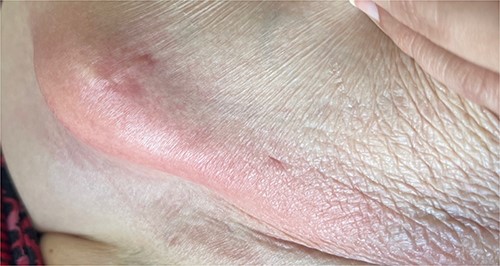

A 65-year-old female with a history of hyperlipidemia, hypertension, hip replacement, lumbar spinal fusion, chronic pain management, and prior laparotomy for endometriosis presented with a 3-day history of nausea, vomiting, and abdominal pain. She had no prior history of diverticulosis or colonoscopy. On examination, she was afebrile and hemodynamically stable. Physical examination revealed left lower quadrant tenderness, swelling, erythema, and fluctuance, suggesting an abdominal wall abscess (Figs 1 and 2). Laboratory tests showed leukocytosis with a count of 24.6 and a positive urinalysis with 2+ leukocytes. A CT scan of the abdomen and pelvis revealed a 3.8 × 3.6 cm air and fluid pocket in the low left anterior abdominal wall, indicative of an abscess likely at the site of a previous drain (Fig. 3). Additionally, there was a 2.8 × 1.8 cm irregular air pocket in the left pelvis, where an abscess had been identified in prior imaging.